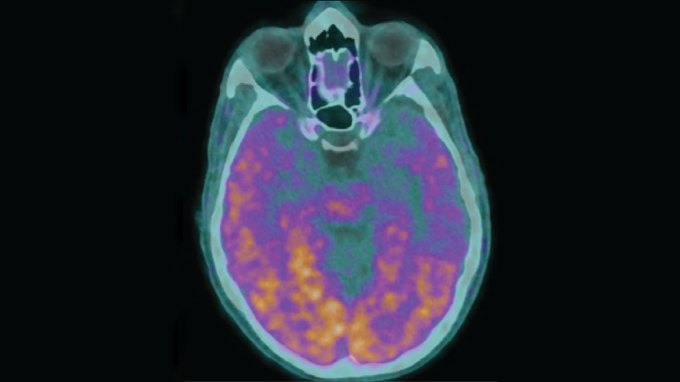

1. Health & Medicine

Under very rare conditions, Alzheimer’s disease may be transmitted

Alzheimer’s isn’t contagious. But contaminated growth hormone injections caused early-onset Alzheimer’s in some recipients, a new study suggests.